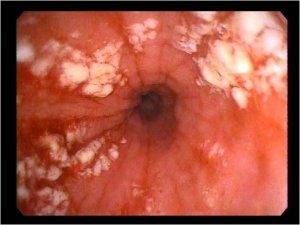

4 степень — самая тяжелая, которая характеризуется стойкими хроническими поражениями слизистой пищевода. На стенках наблюдаются не только обширные язвы и эрозивные дефекты, но и рубцы, которые приводят к стенозу пищевода. Такая степень заболевания имеет самый высокий риск развития злокачественной формы.

Эрозивно-язвенная форма, или эрозивно язвенный рефлюкс эзофагит: к вышеперечисленным поражениям присоединяется появление язв одиночных или множественных. Она протекает по острому или хроническому типу. При этом наблюдается увеличение пищеводных желез, появление кист. Характерным симптомом этой фазы является кашель со слизистыми выделениями.

Псевдомембранозная – появление на слизистой желтоватых фиброзных образований, при отсоединении которых на поверхности эпителия образуются эрозии и язвы. Характеризуется наличием кашля и рвоты с примесью пленок фибрина.